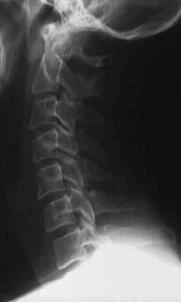

TRAUMA CERVICALA

Incidenta laterala Incidenta

laterala Incidenta

antero-posterioara

Aspect normal Imagine

incompleta Aspect

normal

Incidenta occipitomentala (odontoida)

Aspect normal Incidenta

oblica

Aspect normal

Incidenta oblica Incidenta laterala Incidenta antero-posterioara

Aspect normal Aspect normal Aspect normal